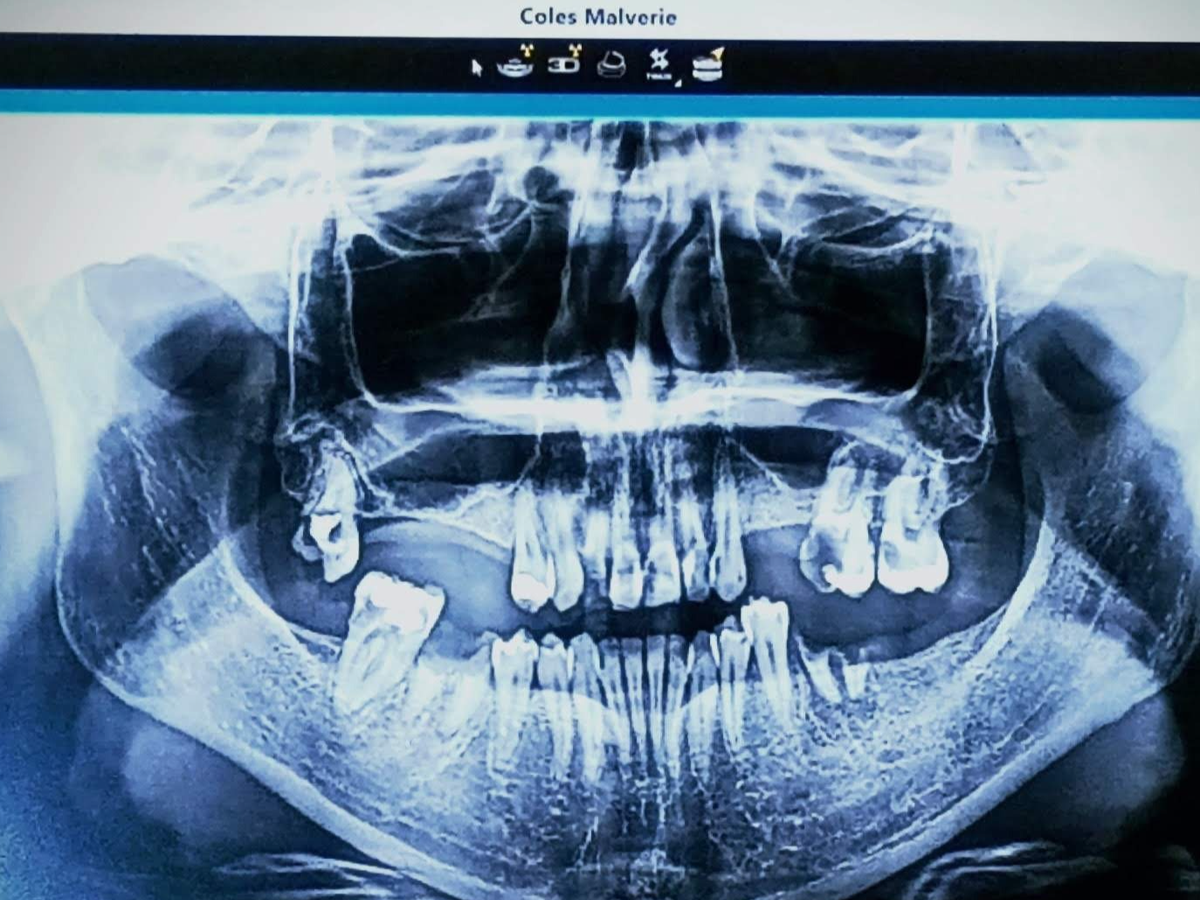

My name is Malverie, and I am reaching out to my community for support as I face a significant medical challenge. I am in need of permanent dentures or dental implants, which are essential not only for my personal confidence and oral comfort but also for protecting my oral health and potentially my overall well-being. This journey has been difficult, and the costs associated with these procedures are more than I can manage on my own.